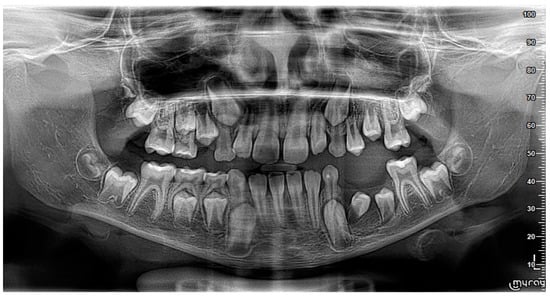

2. Case Report